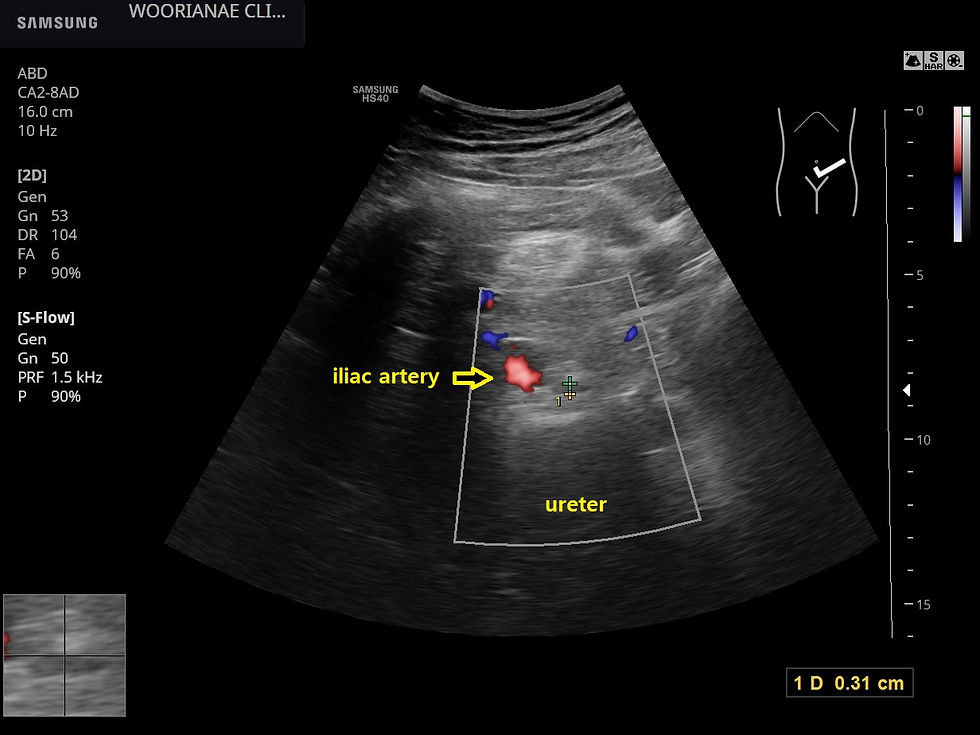

남자로서 큰 체구이므로 소장의 공기에 가려 잘 보이지 않으나 요관의 두번째 협착부인 장골동맥 상방을 관찰하려는 노력을 하였음에도 결석은 발견하지 못하였다.